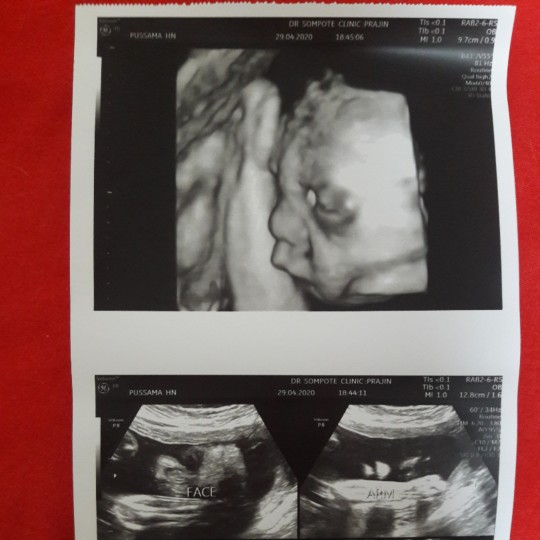

ลูกชายค่ะ 29 weeks 🥰

เหมือนพ่อเป๊ะๆค่า